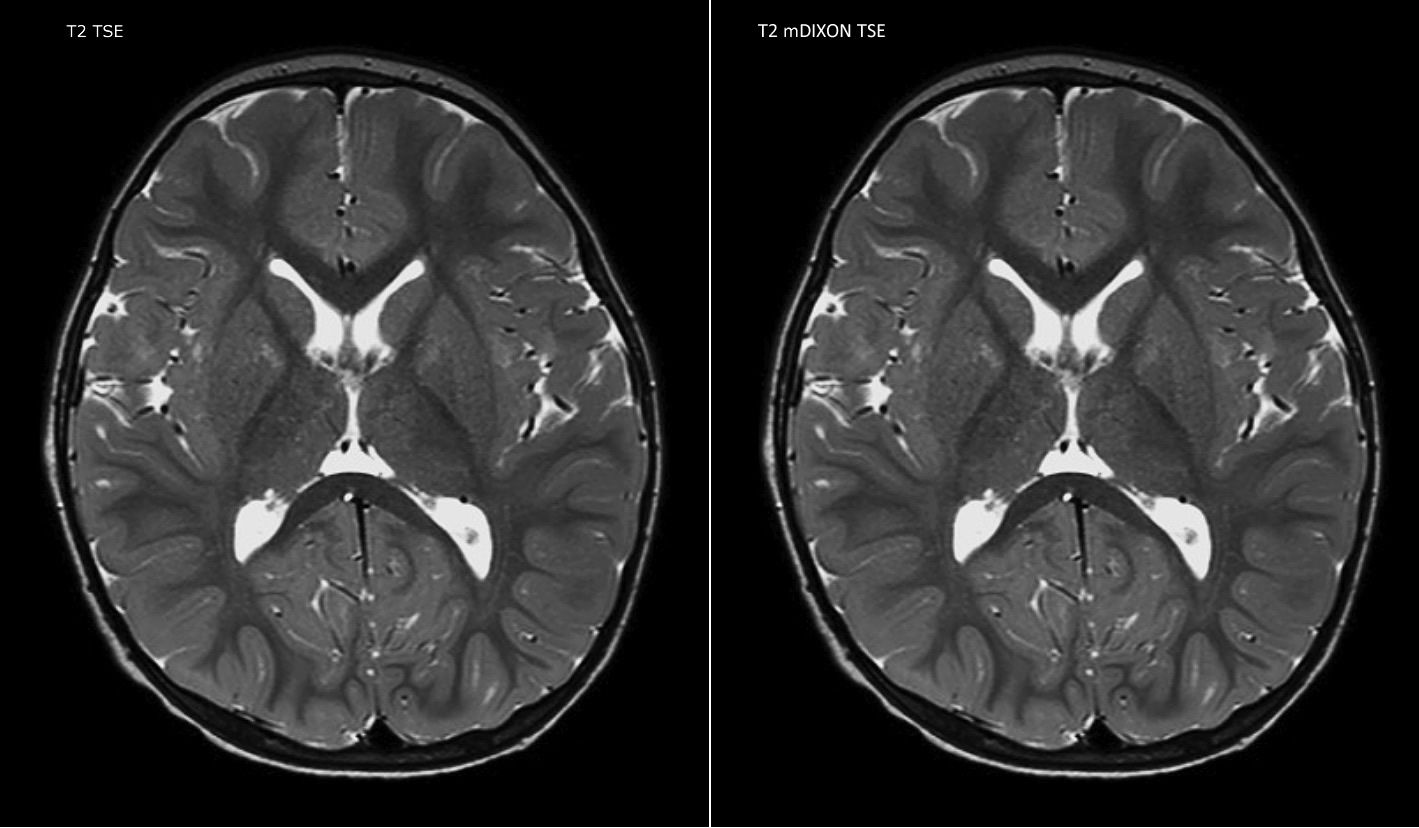

“mDIXON TSE has been one of the most significant improvements in imaging sequences that we have utilized to date at PCH,” says Dr. Miller. “Its multi-parametric acquisition allows us to obtain fat suppressed images and equivalent non-fat suppressed T2 images all in the same sequence. In addition, prior methods of fat suppression could be artifactually corrupted by poor patient anatomy or poor operator application, but with mDIXON we now have a robust and reliable method of fat suppression.”

Fat saturation is historically challenging at the ends of fields of view, especially in total spine imaging and in difficult patient anatomy such as the lower regions of the neck. “Due to the unique fat suppression capabilities of mDIXON, however, these challenges no long apply,” says Dr. Miller. “We routinely obtain homogeneous fat suppression under virtually all conditions. It has also led to some efficiencies by not having to repeat sequences because of that technical failure.”

mDIXON TSE makes a difference

“mDIXON TSE is most useful in patients with lesions or abnormalities in the soft tissues such as the face and neck, and for patients with contrast enhancing abnormalities that are mostly visible with fat suppression,” says Dr. Miller. “All our spine imaging now routinely contains mDIXON water-only T2 images, and this allows us to identify pathology that may be obscured by non-fat suppressed imaging such as injuries of the bone. And it’s not necessary to obtain additional standard TSE T2 images because the in-phase mDIXON images are equivalent to standard TSE T2 images.”